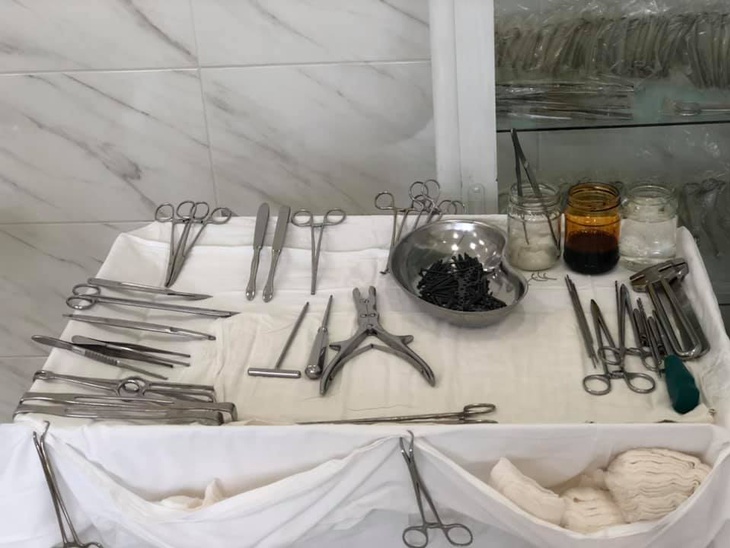

Після проведеного обстеження пацієнтки встановили діагноз: відламковий перелом п‘яткової кістки зі зміщенням.

Під СМА (спинно-мозкова анестезія) провели остеосинтез п‘яткової кістки. Операція пройшла успішно. У пацієнтки були відновлені активні рухи в суглобах стопи.

В операційній працювали: лікар-ортопед-травматолог Родзь Тарас Яремович.

Анестезіологічне забезпечення: лікар-анестезіолог Гідзінський Андрій Миколайович.

Анестезиста: Бадзюнь Лілія Любомирівна.

Сестра медична операційна: Магдюк Людмила Анатоліївна.